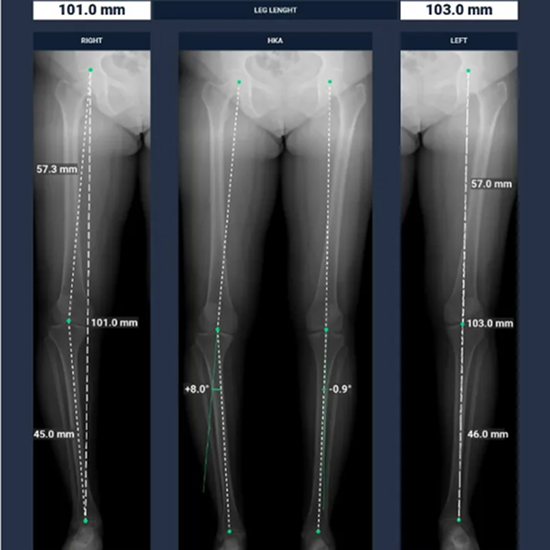

BoneMetrics: Automation of MSK Measurements and Workflow Optimization

With the aid of BoneMetrics, the capture of MSK measurements can be automated. Moreover, workflow optimization can be achieved through unparalleled precision in X-ray and EOS acquisitions.

BoneMetrics automatically performs standard measurements for the feet, legs, pelvis/hips, and spine.

Through accurate point placement and easily understandable displays, the introduction of the software allows you to direct your attention to more critical tasks.